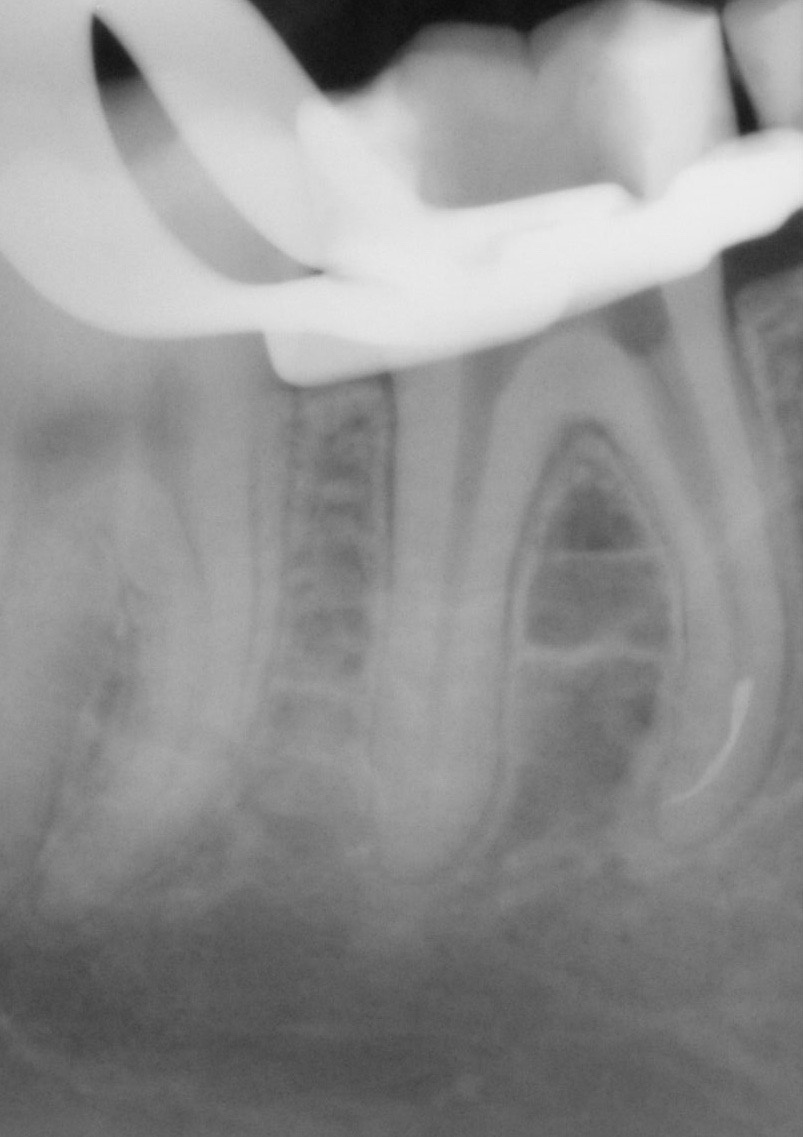

Durch eine Vielzahl von Studien konnte belegt werden, dass die Versorgung mit implantatgetragenem Zahnersatz eine bewährte Behandlungsoption darstellt. Gleichwohl zeigen viele Studien jedoch, dass – wie bei allen Therapiemaßnahmen auch – Komplikationen auftreten können. Diese haben im Allgemeinen biologische oder technische Ursachen. Als häufigste biologische Komplikation findet man die Mucositis (Abb. 1), die Entzündung der periimplantären Gewebe ohne Beteiligung des Alveolarknochens. Nach aktuellen Studien weisen ca. 30 % aller Implantate nach fünf Jahren eine Mucositis auf. Kommt es darüber hinaus zu einer Beteiligung des Alveolarknochens, liegt eine Periimplantitis vor (Abb. 2). Sie tritt nach fünf Jahren bei etwa 10 % der inkorporierten Implantate auf und ist durch den Verlust des periimplantären Alveolarknochens gekennzeichnet. Die Periimplantitis kann, je nach Schweregrad, zum kompletten Implantatverlust führen. Bei einem strategisch wichtigen Implantat kann daraus der Verlust der gesamten prothetischen Versorgung resultieren und eine operativ sowie finanziell aufwendige Neuversorgung erforderlich werden (Abb. 3).